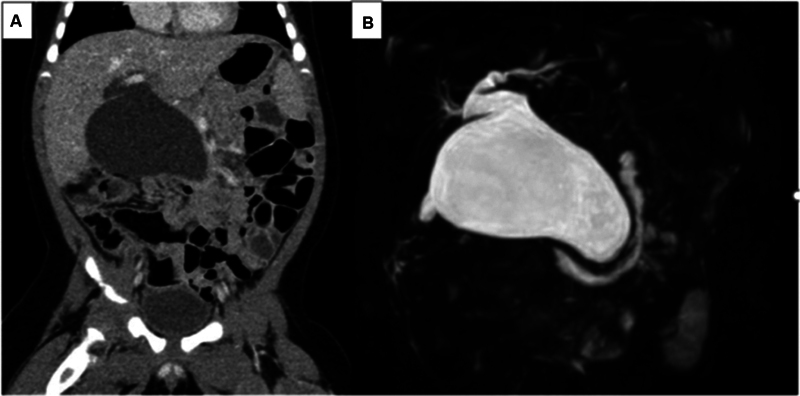

The patient was a boy with congenital hydronephrosis who had undergone ultrasonography every month for follow-up. At 4 months of age, ultrasonography incidentally showed an intra-abdominal cyst. Computerized tomography (CT) and magnetic resonance cholangiopancreatography revealed congenital biliary dilatation (5-cm type Ia [Todani classification]) ( Fig. 1A, B ). A definitive pancreaticobiliary maljunction and bile duct anomaly were not detected preoperatively. At 7 months of age, we performed extrahepatic bile duct resection and hepaticojejunostomy with a five-port layout.